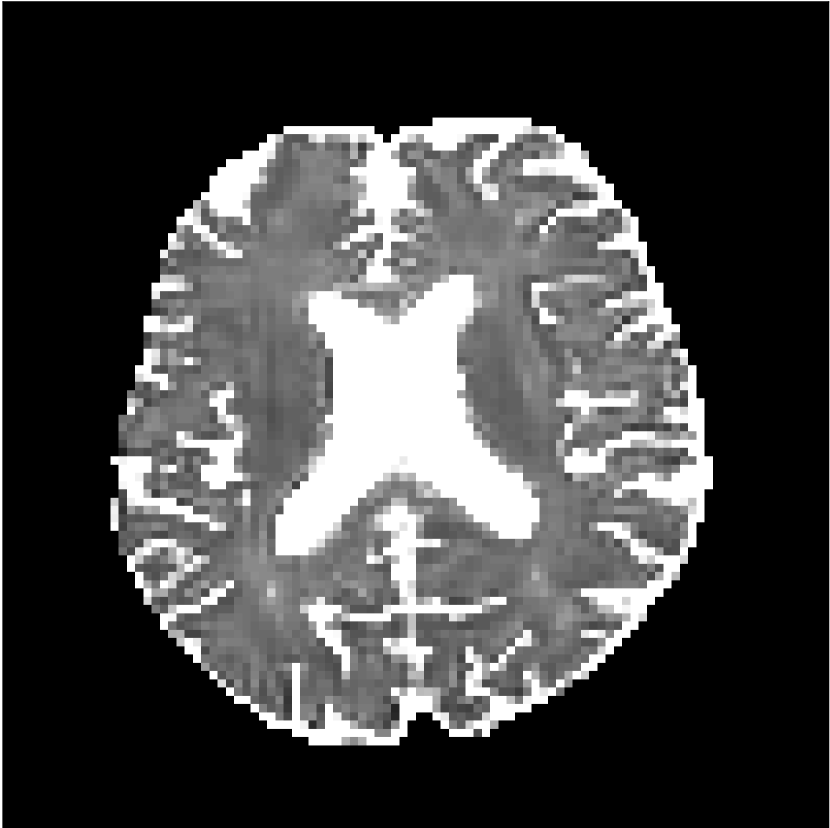

Figure 10 compares mean diffusivity maps across various partial Fourier factors between the CCNN and state-of-the-art methods.

No PF

7/8 PF

6/8 PF

5/8 PF

SoA

Refer to caption

MD, μ𝜇\mum2/ms

CCNN

Figure 10: Comparison of mean diffusivity (MD) parameter maps across PF factors of 5/8ths, 6/8ths, 7/8ths, and without PF (No PF). The methods include state-of-the-art (SoA) and CCNN methods. Without partial Fourier, both methods are similar; however, as the PF factor increases, substantial artifacts are introduced in the SoA method, particularly around the lateral ventricles. The CCNN method is able to reduce the introduction of artifacts.

The methods perform similarly without partial Fourier acceleration, but as partial Fourier acceleration increases, the image is continually degraded in the SoA method, with "black voxels" appearing around the lateral ventricles. The CCNN method mitigates the appearance of these artifacts in the parameter maps.